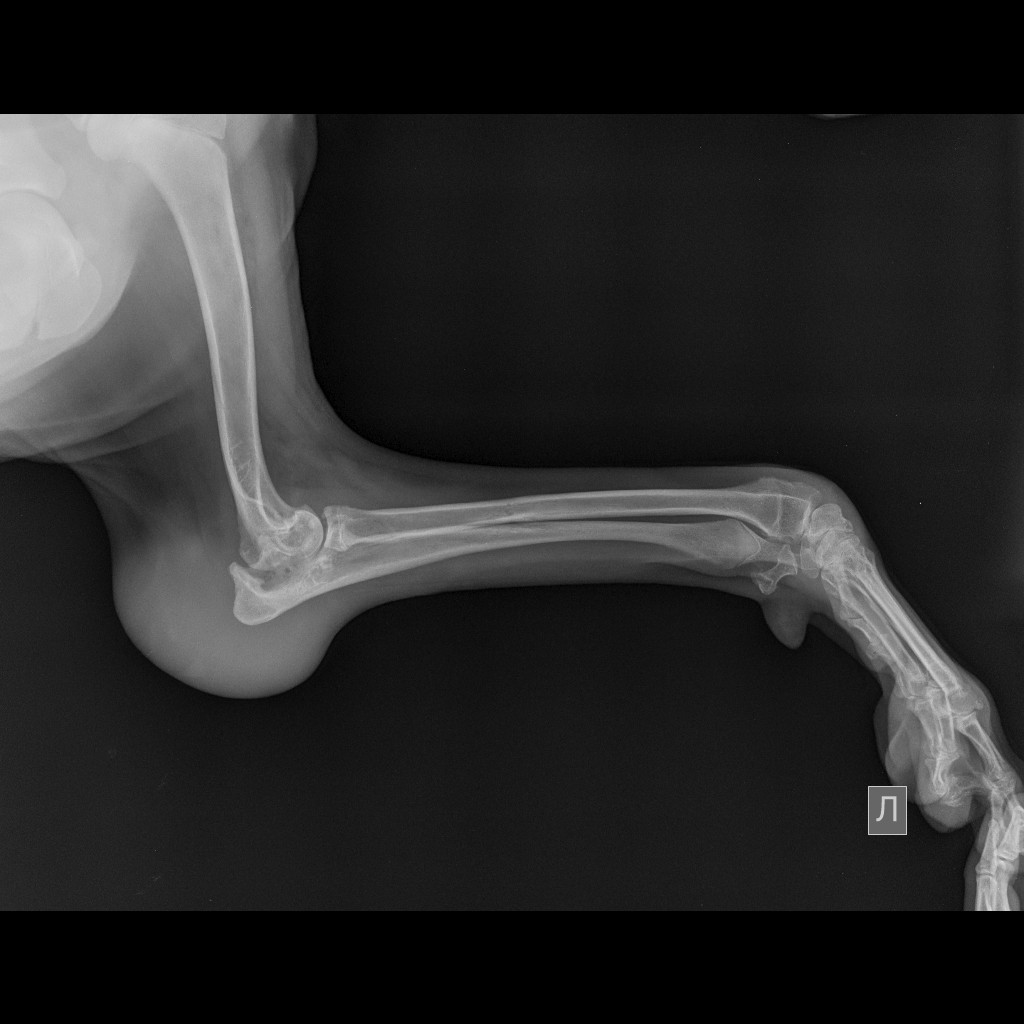

После операции и продолжительного лечения, задняя лапка полностью восстановилась, а вот передняя, после артопротезирования, которое сделали в городе Лида в клинике «Кот Бегемот», требует реабилитации.